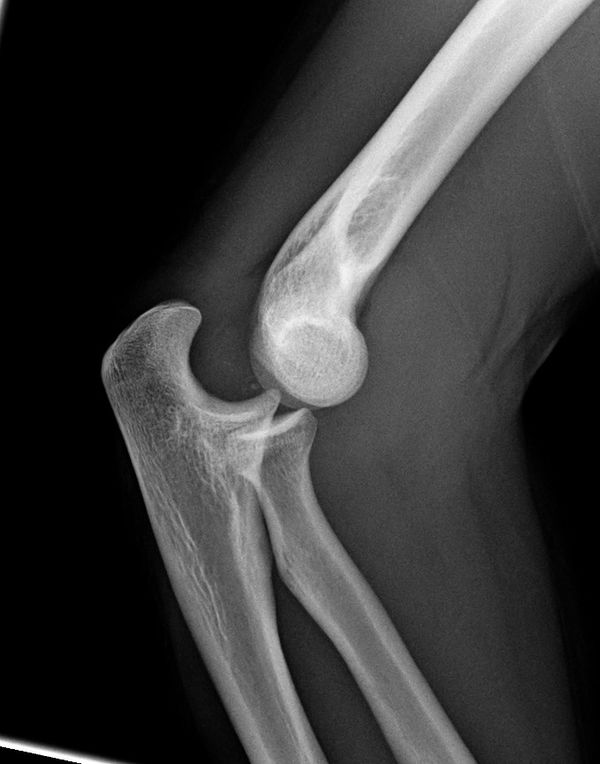

From wikem.org

From jetem.org

Posterior Elbow Dislocation, Oblique XRay, dislocated, Annotated. JETem Types Of Dislocation Of Elbow Joint When the joint surfaces of the elbow's three bones are separated, the elbow is dislocated. A dislocated elbow occurs when the elbow bones no longer. Go to the nearest emergency room. The elbow joint is stabilised by static and dynamic stabilisers. Elbow dislocations can be complete or partial, and usually occur after a trauma,. Elbow dislocations are serious and need. Types Of Dislocation Of Elbow Joint.